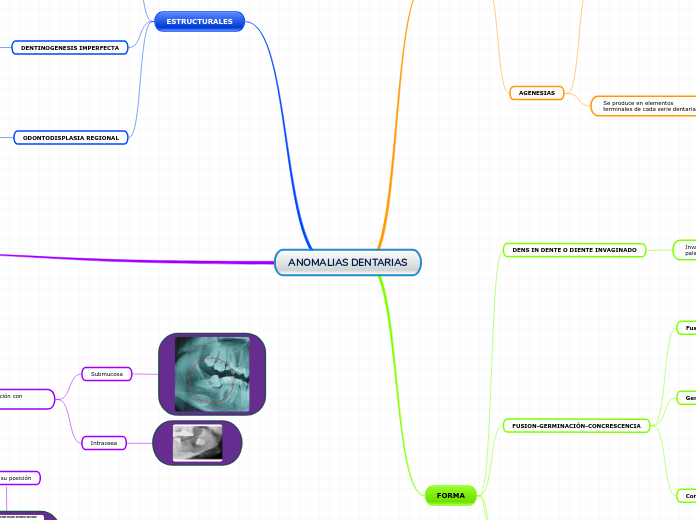

ANOMALIAS DENTARIAS

NÚMERO

AGENESIAS

FORMA

DENS IN DENTE O DIENTE INVAGINADO

FUSION-GERMINACIÓN-CONCRESCENCIA

TAURODONTISMO

MICRODONCIA-MACRODONCIA

ESTRUCTURALES

DENTINOGENESIS IMPERFECTA

ODONTODISPLASIA REGIONAL

ALTERACIONES DE POSICIÓN

RETENIDOS